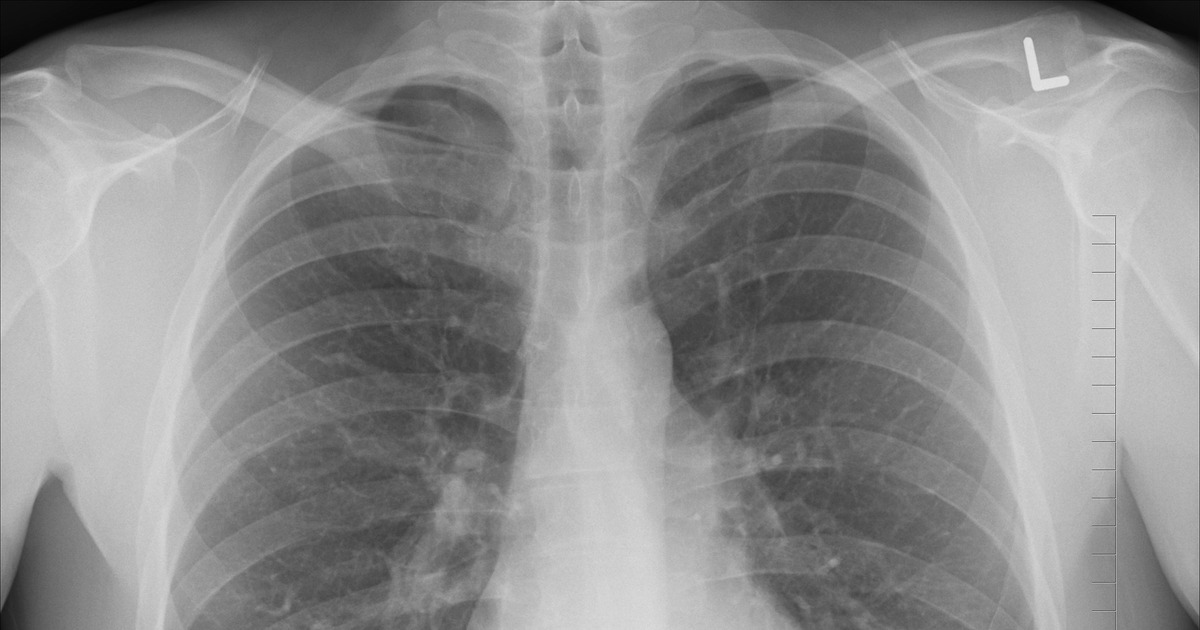

Выраженный дефицит витамина D значительно повышает риск госпитализации пожилых людей из-за инфекций дыхательных путей. К такому выводу пришли учёные из Университета Суррея, результаты исследования опубликованы в The American Journal of Clinical Nutrition.

Анализ был проведён на основе данных 36 258 участников Британского биобанка — взрослых среднего и пожилого возраста. Для этой возрастной группы инфекции нижних дыхательных путей, включая бронхит и пневмонию, остаются одной из ведущих причин смертности.

Исследователи установили, что у людей с крайне низким уровнем витамина D в крови — менее 15 нмоль/л — риск госпитализации по поводу респираторных инфекций был на 33% выше по сравнению с участниками, у которых концентрация витамина D составляла 75 нмоль/л и более. При этом увеличение уровня витамина D на каждые 10 нмоль/л сопровождалось снижением риска госпитализации примерно на 4%.

Авторы напомнили, что витамин D играет роль не только в поддержании здоровья костей и мышц, но и участвует в работе иммунной системы, влияя на противовирусные и антибактериальные механизмы защиты организма, сообщает Газета.ру.